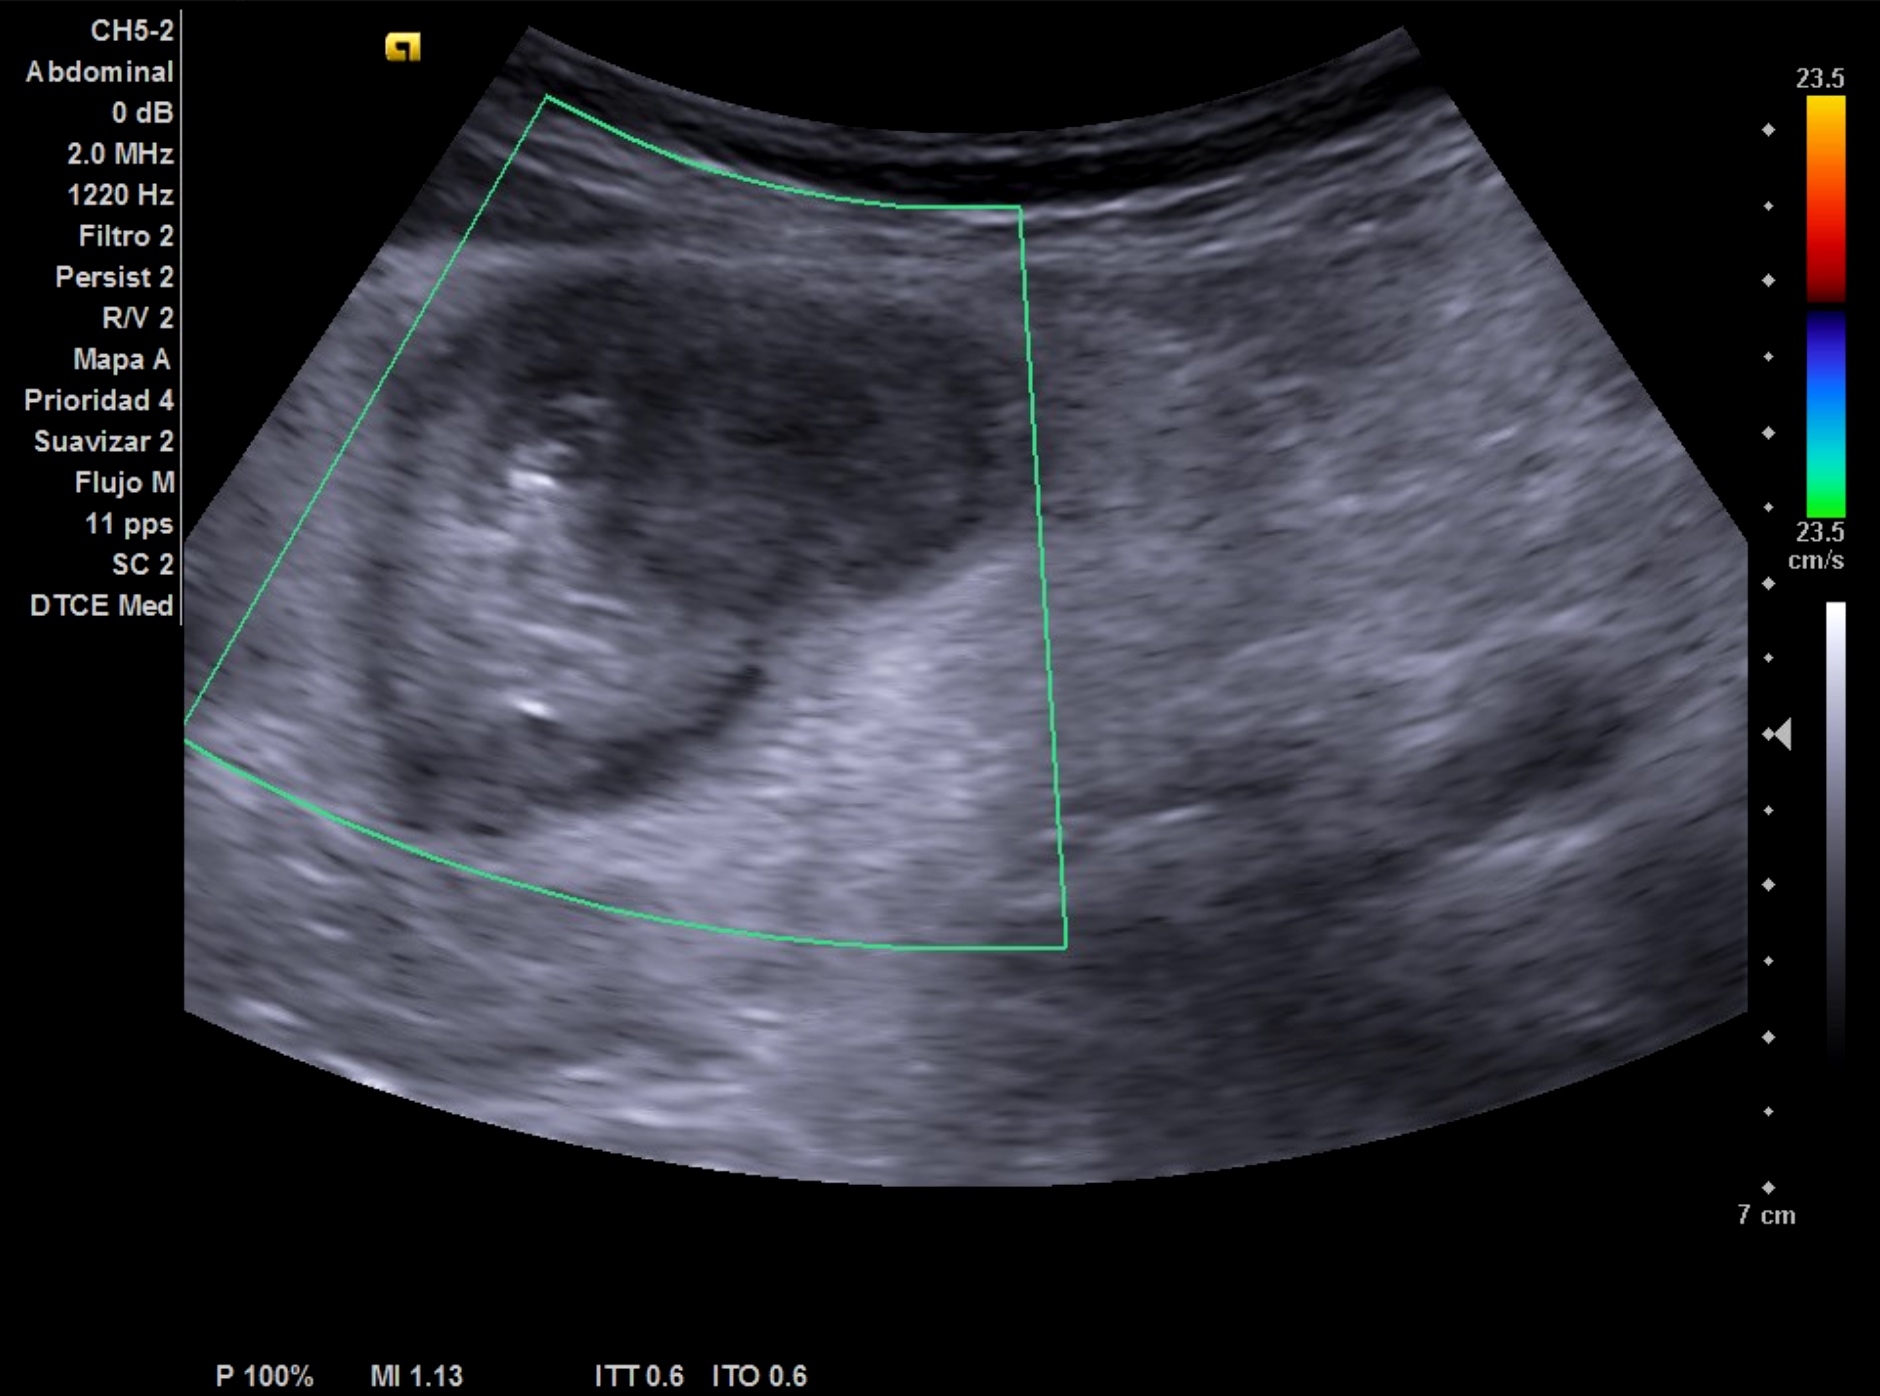

- Hígado de tamaño y eco-estructura normal. Riñón derecho normal. Imagen localizada anterior a riñón derecho, redondeada-ovalada, hipoecoica con zonas hiperecoicas en su interior, vascularizada probablemente compatible con signo de pseudo-riñón con sospecha de neoplasia de colon.